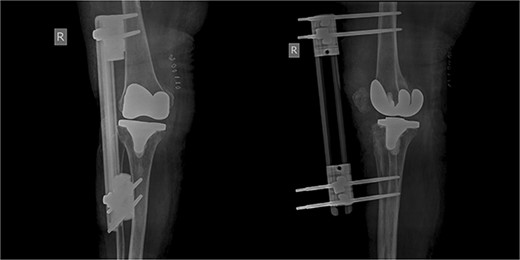

The patient underwent a medial-pivot design TKA (Evolution Medial-Pivot Knee System, Microport, China). Intraoperatively, a full ROM was achieved only after extensive soft tissue and bone releases. The extension gap was limited by significant hamstring spasticity, and a proper extension gap was attained after additional anterior femoral cut. Early postoperative recovery was uneventful (Fig. 2). On the third postoperative day, the patient complained of severe knee pain accompanied by excessive swelling during kinesiotherapy. Clinical examination showed a posterior sag sign at 30° of flexion (Fig. 3). No signs of neurovascular deficit were obvious. A knee X-ray revealed posterior TKA dislocation and a small, non-displaced femoral fracture (Fig. 4). The tibial component was reducible, but redislocation occurred with the knee extended over 90°, indicative of severe instability. Laboratory investigations, including erythrocyte sedimentation rate and C-reactive protein, were normal. A knee arthrocentesis was performed with no substantial findings. Two botulinum toxin injections (200 IU) to the hamstrings were performed without improvement. Local muscle hypertonia was evaluated through a neurological examination and a brain computed tomography scan, with no remarkable findings. The patient’s history included intramedullary nailing of the right femur due to an intertrochanteric fracture 8 months before the TKA.

The patient was reoperated, where a more extensive release of the hamstrings was performed, obtaining full extension. The knee was stabilized using a lateral external fixator (Fig. 5). Muscle biopsies were obtained, indicating signs of chronic inflammation. Full weight bearing, using a walker, was permitted from the first postoperative day without substantial complaints.